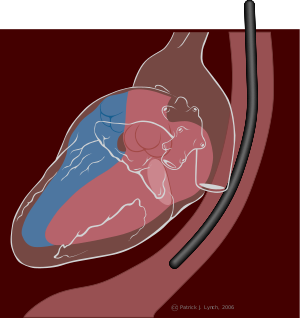

يتم تخطيط صدى القلب عبر الصدر إنگليزية: TTE transthoracal echocardiography بوضع رأس المسبار الذي يبث موجات فوق صوتية بشكل مقطعي على الجلد عند جدار الصدر ما بين ضلعين، للوصول إلى تصوير للقلب من عدة جوانب، والحصول على مقاطع متعددة لحجرات القلب. عادة ما يُطلب من المريض الكشف عن صدره والاستلقاء إلى الجانب الأيسر. من ناحية مبدئية هناك نقطتان رئيسيتان لتخطيط صدى القلب، الأولى بالجانب الأيسر الأعلى لعظم القص، والثانية في المسافة بين الأضلاع المماثلة لقمة القلب.

1. السطر الأول يمثل المقاطع التي نحصل عليها عند تخطيط صدى القلب باستخدام النقطة المماثلة لقمة القلب.

2. السطر الثاني يمثل المقاطع التي نحصل عليها عند تخطيط صدى القلب من الجانب الأيسر لعظمة القص. |